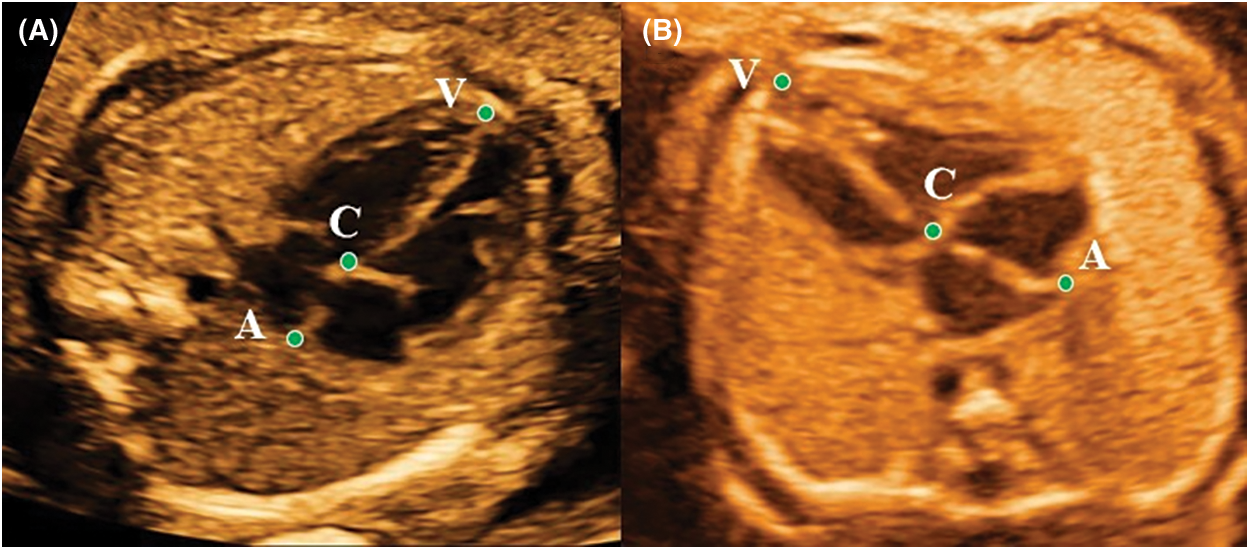

Measurements of conventional parameters, including 2-dimensional fetal cardiac structural values, the Doppler parameters, and the umbilical and cerebral Doppler measurements, a total of 48 measurements were obtained based on the guidelines published by the American Society of Echocardiography [20]. The special parameters, including heart length (HL), ventricle length (VL), atrium length (AL), and the AVLR (AL/VL ratio), a total of 8 variables were acquired on the four-chamber view (4CHV) at the end diastole (ED) and end systole (ES). All special parameters were calculated with an image review. ED was a frame just prior to the start of the systolic period. At this time, both the atrioventricular valve and the semilunar valve were closed, and the ventricle was the largest. ES was a frame before the start of the diastolic period. And both the atrioventricular valve and the semilunar valve were also closed at this moment, but the ventricle was the smallest. In the ED, measuring methods of HL and VL were consistent with Machlitt’s [17]. But AL in the normal group and cohort 3 was the measurement from the top of the atrium to the attachment point of the mitral valve at the interventricular septum (Fig. 1A); and in AVSDs, AL was the measurement from the roof of the atrium to a closed common atrioventricular valve (Fig. 1B). In the ES, the measurement rule was consistent with that in the ED. All values were measured twice by the same operator who had 5 years of FE experience, and the average value was taken.

Figure 1: The VL (point V to C), AL (point C to A), and HL (point V to A) measured in end-diastolic period on the apical four-chamber view in the normal fetus at 24.3 gestational weeks (A) and in the AVSDs fetus at 25.1 gestational weeks (B). AVLR = AL/VL